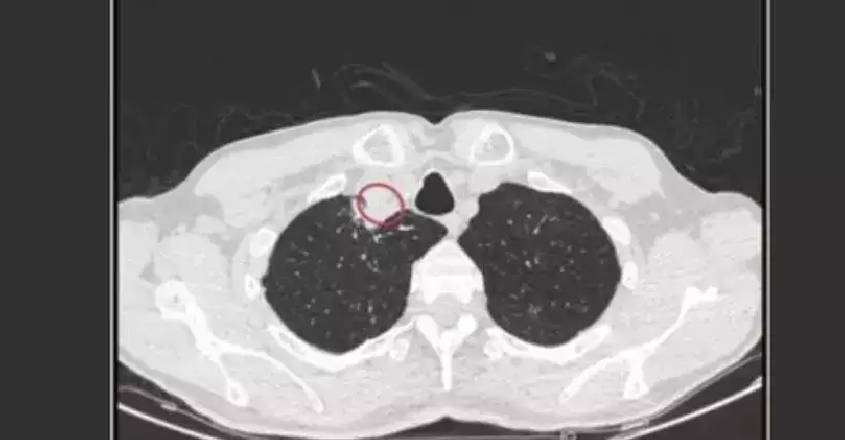

കൂൺ അടക്കമുള്ള ചീയുന്ന വസ്തുക്കളിൽ പഠനം നടത്തിവരികയായിരുന്നു ഇദ്ദേഹം. തൊണ്ടയടപ്പ്, ചുമ, തളർച്ച എന്നിവയുണ്ടായ ഇദ്ദേഹത്തിന് മൂന്ന് മാസത്തോളം ഭക്ഷണം ഇറക്കാൻ സാധിക്കാത്ത അവസ്ഥയായിരുന്നു. ഏത് ഫംഗസാണ് ബാധിച്ചതെന്ന് കണ്ടെത്താൻ സാധിച്ചില്ല. ഒടുവില്‍ സി.ടി സ്‌കാനില്‍ കഴുത്തിനു താഴെയായി ശ്വാസനാളത്തില്‍ മുഴ കണ്ടെത്തി. കോൺഡ്രോസ്റ്റിറം പർപ്യുറം എന്ന ഫംഗസ് ആകാനാണ് സാധ്യതയെന്ന് കൊൽക്കത്ത അപ്പോളോ ആശുപത്രിയിലെ ഡോക്ടർമാരായ സോമ ദത്ത, ഉജ്ജയിനി റേ എന്നിവർ അറിയിച്ചു.